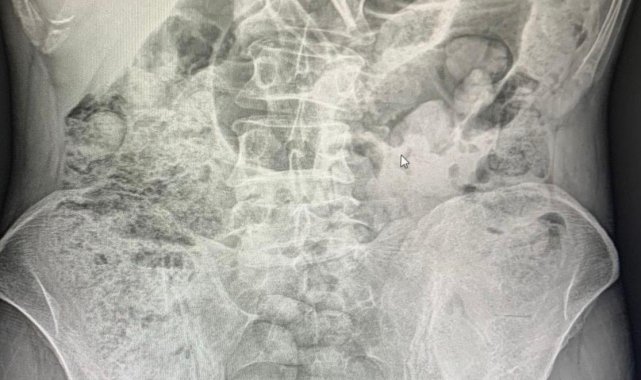

Siirt Emniyet Müdürlüğü Narkotik Suçlarla Mücadele Şube Müdürlüğü görevlilerince 14 Aralıkta Baykan Şehit Bünyamin Torgut Polis Uygulama Noktasında durdurulan iki araçta, batı illerine uyuşturucu madde sevk etmek için uyuşturucu maddeleri özel yöntemler kullanarak paketleyerek yutmak yöntemiyle mide kısmında taşıyan İran uyruklu 3 kadın 1 erkek şahıs yakalanmıştı. Şahısların midelerinde bulunan uyuşturucu maddeler 10 gün devam eden hastane süreci sonucunda cerrahi yöntemler kullanılarak çıkartıldı.

Şüpheli şahısların midelerinden 119 paket halinde 1 kilo 597 gram uyuşturucu madde çıkartıldı. Zanlılar, sevk edildikleri adli makamlarca tutuklanarak cezaevine sevk edildi.